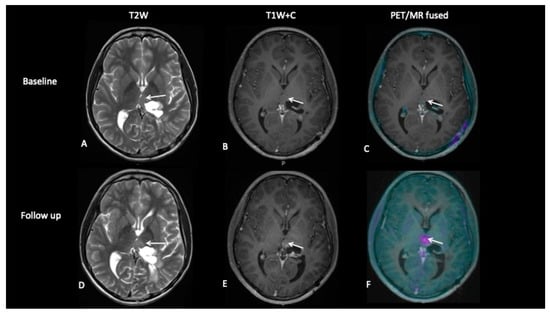

- Patient 4: Tumour Progression Versus Pseudoprogression

A 15-year-old male with a large tumour involving the left thalamus underwent gross resection of the thalamic tumour, and the histology confirmed this to be a high-grade astrocytoma with the known histone H3F3A K27M mutation. A response assessment scan after 6 months of chemotherapy (Figure 7) suggested minimal enhancement in the residual tumour that was thought to be pseudoprogression. However, FDOPA showed tracer uptake consistent with tumour progression.

Figure 7.

The baseline imaging post-surgery demonstrates residual non-enhancing tumour in the medial right thalamus (A–C). Follow-up imaging demonstrates the non-enhancing component (D) and mild enhancement of this component (E), uncertain for tumour progression or pseudoprogression, but the FDOPA (F) demonstrates increased uptake consistent with tumour progression.